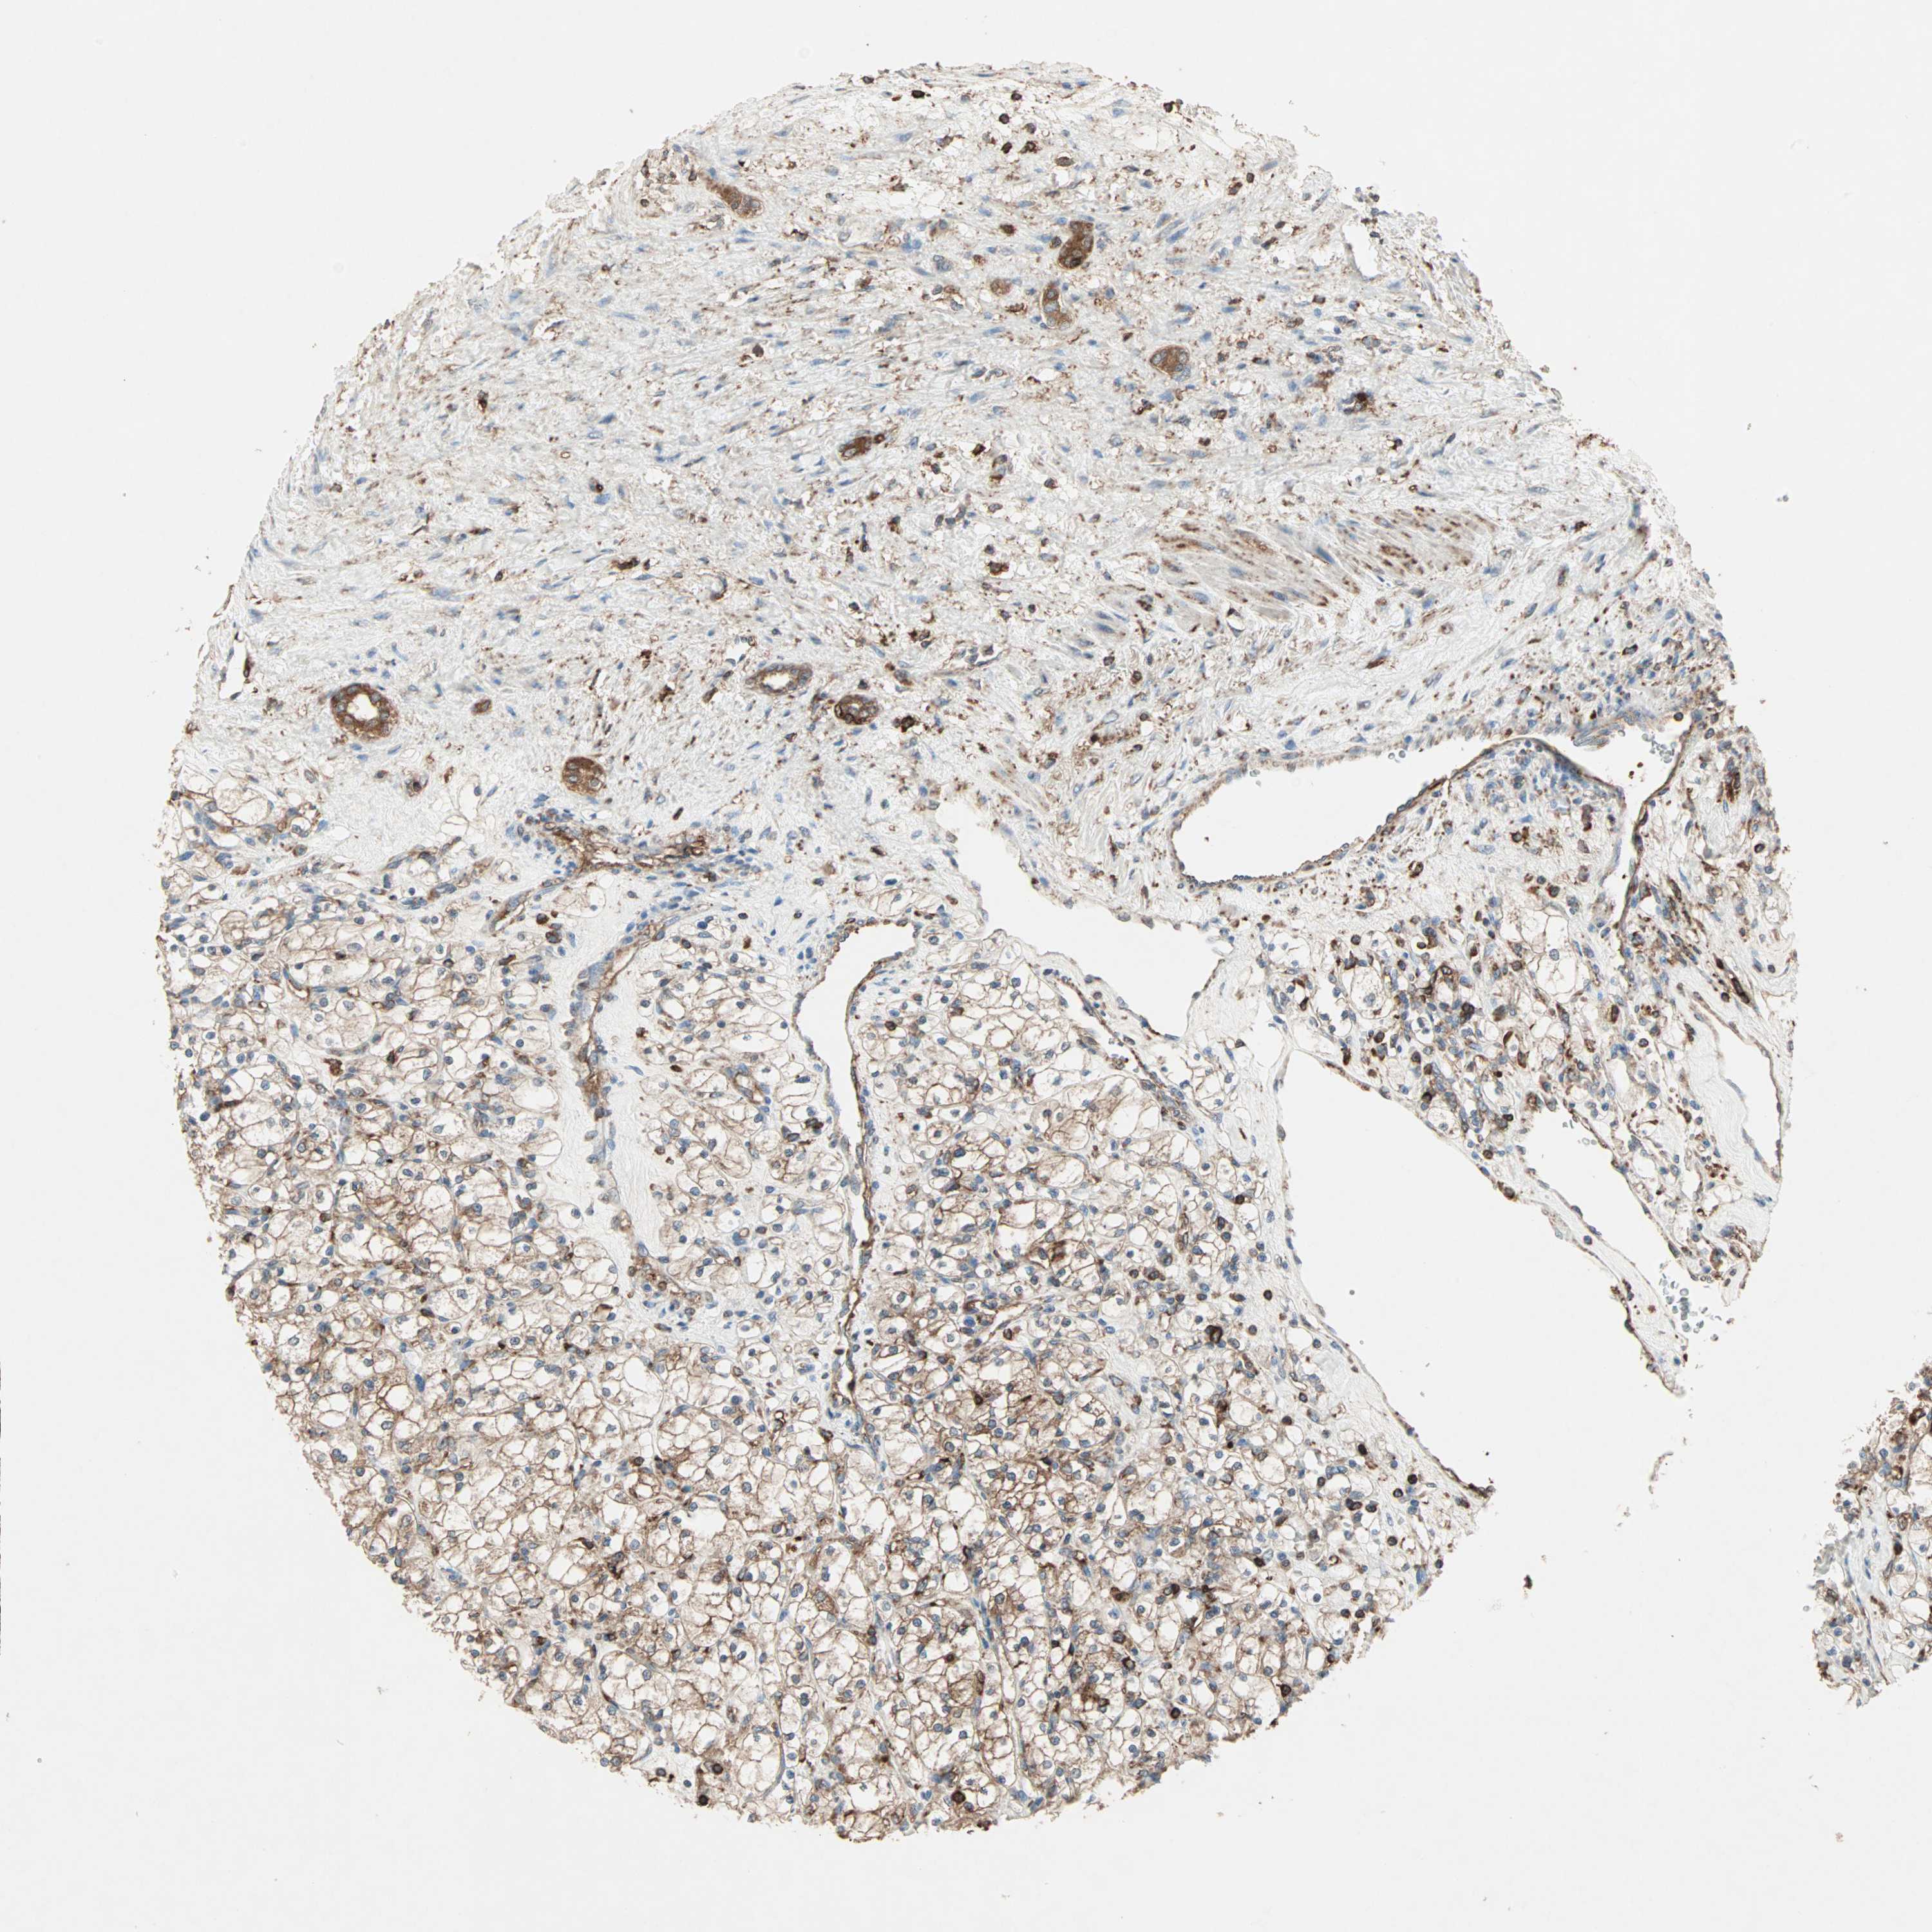

KIDNEY RENAL CLEAR CELL CARCINOMA (VALIDATION) - Interactive survival scatter ploti

The Survival Scatter plot shows the clinical status (i.e. dead or alive) for all individuals in the patient cohort, based on the same data that underlies the corresponding Kaplan-Meier plots. Patients that are alive at last time for follow-up are shown in blue and patients who have died during the study are shown in red.

The x-axis shows the expression levels (FPKM) of the investigated gene in the tumor tissue at the time of diagnosis. The y-axis shows the follow-up time after diagnosis (years). Both axes are complimented with kernel density curves demonstrating the data density over the axes. The top density plot shows the expression levels (FPKM) distribution among dead (red) and alive patients (blue). The right density plot shows the data density of the survived years of dead patients with high and low expression levels respectively, stratified using the cutoff indicated by the vertical dashed line through the Survival Scatter plot. This cutoff is automatically defined based on the FPKM cutoff that minimizes the p-score. The cutoff can be changed by dragging the vertical line or by entering a cutoff value in the square labeled "Current cut-off".

Under the Survival Scatter plot the p-score landscape (black curve; left axis) is shown together with dead median separation (red curve; right axis). Dead median separation is the difference in median mRNA expression between patients who have died with high and low expression, respectively. It is calculated as follows: median FPKM expression of dead patients with high expression - median FPKM expression of dead patients with low expression. This is intended to aid the user in visually exploring custom cutoffs and the associated p-scores and dead median separation.

Individual patient data is displayed and can be filtered by clicking on one or more of the category buttons on the top of the page. Categories describing expression level and patient information include: high, low, alive, dead, female, male and tumor stages. The scale of the x-axis can be toggled between linear and log-scale by clicking on the "x log" button. Mouse-over function shows TCGA ID, patient information and mRNA expression (FPKM) for each patient.

& Survival analysisi

Kaplan-Meier plots summarize results from analysis of correlation between mRNA expression level and patient survival. Patients were divided based on level of expression into one of the two groups "low" (under cut off) or "high" (over cut off). X-axis shows time for survival (years) and y-axis shows the probability of survival, where 1.0 corresponds to 100 percent.

Survival analysis data not available.

TCGA RNA samplesi

RNA-seq data is reported as average FPKM (number Fragments Per Kilobase of exon per Million reads), generated by the The Cancer Genome Atlas (TCGA) .

Normal distribution across the dataset is visualized with box plots, shown as median and 25th and 75th percentiles. Points are displayed as outliers if they are above or below 1.5 times the interquartile range. FPKM values of the individual samples are presented next to the box plot.

Average pTPM 0.0

Number of samples 100